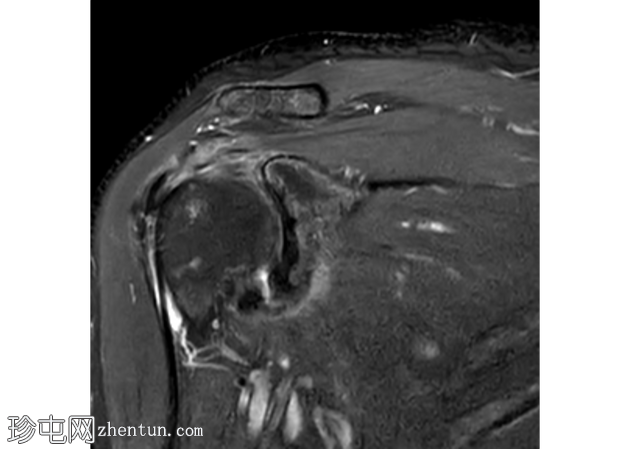

轴向

PD

冈上肌腱滑囊侧存在部分厚度撕裂,肌腱物质内分层延伸约2厘米,与滑囊侧分层部分厚度撕裂相符。伴有间质性肩胛下肌腱(SST)撕裂。冈上肌体积轻度减少。

冠状面可见盂唇上方T2高信号,提示SLAP损伤。SLAP损伤延伸至肱二头肌长头,矢状面清晰可见。肱二头肌长头腱正常位于肱二头肌沟内,周围积液极少。

肩袖分层撕裂通常被描述为肌腱物质的水平分裂。

其特征性表现是充满液体的裂隙,将关节面和滑囊肌腱层分开,形成“双层”外观。

关节面保持大致连续,而滑囊面不连续且回缩。分层会严重损害肌腱的生物力学。